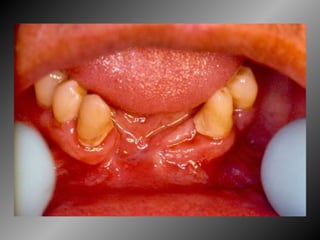

25 -  L.C.S., sexo masculino, 18 anos de idade, se apresentou com queixa de aumento de volume na gengiva entre os dentes 23  e  24.  Pelo  exame  clínico,  constatamos  a  presença  de  um  nódulo  séssil,  de  contornos  irregulares,  coloração  avermelhada, com sangramento abundante ao mínimo toque e evolução de 1 ano. O paciente apresentava higiene bucal precária com presença de placa bacteriana e tártaro. Com base no quadro clínico, o diagnóstico é: a) Fibroma e granuloma piogênico. b) Granuloma piogênico e hiperplasia fibrosa inflamatória. c) Lesão periférica (granuloma) de células gigantes e fibroma. d) Granuloma piogênico e lesão periférica (granuloma) de células gigantes. e) Hiperplasia fibrosa inflamatória e fibroma.

Granuloma Piogênico Lesão Nodular Séssil ou pediculada Avermelhada ou vinhosa Sangramento espontâneo e áreas de micro-ulceração superficial

Granuloma Piogênico Lesões nodulares de coloração avermelhada ou vinhosa Provavelmente uma reação inflamatória exagerada ao trauma menor Crescimento rápido, às vezes sangramento espontâneo Ocorre em qualquer idade mas parece mais freqüente em adultos jovens e adolescentes  Localização mais comum: gengiva (NEVILLE,2001)

Granuloma Piogênico Lesões mais antigas, são menos vasculares e mais fibrosas Papila interdental e regiões anteriores são áreas preferenciais, principalmente por vestibular (BORK,1996)

Granuloma Periférico de Células Gigantes Lesões nodulares de coloração avermelhada ou vinhosa Provavelmente uma reação inflamatória exagerada ao trauma menor Crescimento rápido, às vezes sangramento espontâneo Ocorre em qualquer idade mas parece mais freqüente em homens antes dos 16 anos de idade a após esta faixa torna-se duas vezes mais freqüente em mulheres Localização mais comum: gengiva

Granuloma (Lesão) Periférico de Células Gigantes A excisão cirúrgica deve ser antecedida de exame radiográfico, pois lesão não completamente removida e/ou com infiltração óssea, pode recorrer

Granuloma Piogênico LesãoNodular Séssil ou pediculada Avermelhada ou vinhosa Sangramento espontâneo e áreas de micro-ulceração superficial

Granuloma Piogênico Lesõesnodulares de coloração avermelhada ou vinhosa Provavelmente uma reação inflamatória exagerada ao trauma menor Crescimento rápido, às vezes sangramento espontâneo Ocorre em qualquer idade mas parece mais freqüente em adultos jovens e adolescentes Localização mais comum: gengiva (NEVILLE,2001)

Granuloma Piogênico Lesõesmais antigas, são menos vasculares e mais fibrosas Papila interdental e regiões anteriores são áreas preferenciais, principalmente por vestibular (BORK,1996)

Granuloma Periférico deCélulas Gigantes Lesões nodulares de coloração avermelhada ou vinhosa Provavelmente uma reação inflamatória exagerada ao trauma menor Crescimento rápido, às vezes sangramento espontâneo Ocorre em qualquer idade mas parece mais freqüente em homens antes dos 16 anos de idade a após esta faixa torna-se duas vezes mais freqüente em mulheres Localização mais comum: gengiva

Granuloma (Lesão) Periféricode Células Gigantes A excisão cirúrgica deve ser antecedida de exame radiográfico, pois lesão não completamente removida e/ou com infiltração óssea, pode recorrer